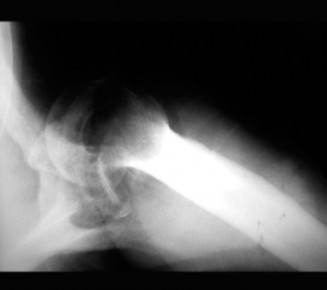

A 47-year-old, right-hand-dominant male presents to your clinic complaining of right shoulder weakness for th…

A 21-year-old, right-hand-dominant, male, college swimmer presents to clinic complaining of gradually worseni…

A left-hand-dominant, 66-year-old female is sent to your office for shoulder pain, possibly a rotator cuff te…

A 24-year-old, left-hand-dominant, businesswoman presents to clinic with 2 days of right shoulder pain. Two d…